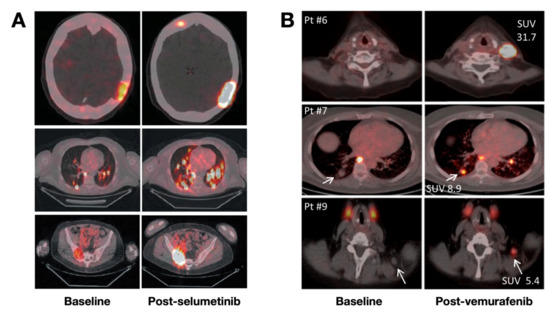

Thyroid Cancer Explore vol.3 no.2(2201 「Thyroid Cancer Expl Thyroid Cancer Treatment (PDQ®) - NCIの詳細情報

Thyroid Cancer Treatment (PDQ®) - NCI。Comparative Analysis of Metastatic Thyroid Carcinoma versus。The Role of Positron Emission Tomography/Computed Tomography。

ThyroidCancerExploreVol.3No

「ThyroidCancerExpl

Thyroid Cancer - Endotext - NCBI Bookshelf

Thyroid Cancer - Endotext - NCBI Bookshelf

■商品名■

ThyroidCancerExploreVol.3No

「ThyroidCancerExpl